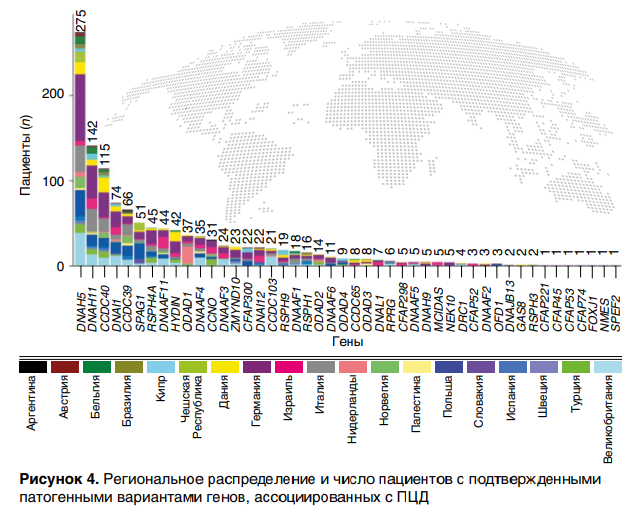

ПЦД — генетически детерминированное заболевание, в связи с чем ключевую роль играет метод ДНК-диагностики. Наибольшее предпочтение отдается полному секвенированию генома, при котором в 74–76 % случаях выявляются причинно-значимые гены. По данным многоцентрового анализа 1236 пациентов с ПЦД выявлены патогенные варианты в 46 генах, связанных с фенотипом болезни. Наиболее часто обнаруживают варианты генов DNAH5, DNAH11, CCDC40, DNAI1, CCDC39, SPAG1 (рис. 4).